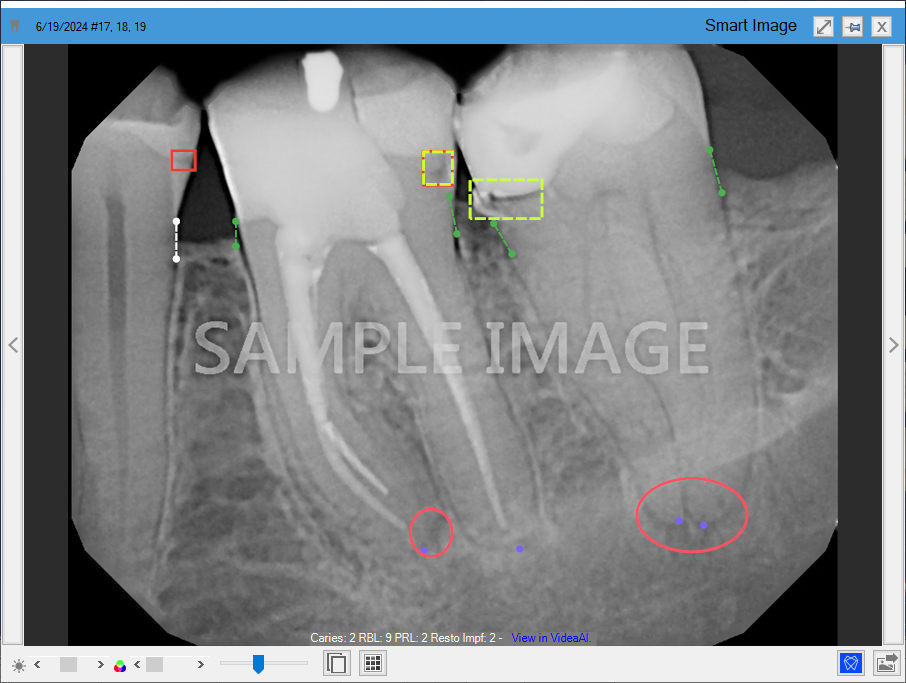

Detecting caries in the enamel (dotted line yellow rectangles) and dentin (solid line red rectangles) on all primary and secondary teeth of patients three years and older. This eliminates the need for manual analysis of all primary and secondary teeth, saving you and your hygienists time.

Measuring interproximal Radiographic Bone Levels in bitewings and Periapical Radiographs (PAs) for patients who are at least 12 years old. Bone level detection is only possible with mesial and distal surfaces. RBL measurements appear as green, yellow, orange, or red dotted lines.

Detecting periapical radiolucency (PRL) for patients 22 years and older to more effectively identify bone demineralization due to infections around root apices, cysts, and other causes. PRL is indicated by a red circle or oval.

Detecting restoration imperfections in patients 22 years and older by identifying imperfect crown and filling margins and voids. A restoration imperfection is indicated by a yellow rectangle.

In Figure 3, caries are indicated by a red square, RBL is indicated by vertical dotted lines, PRL is indicated by red ovals, and restorative imperfections are indicated by yellow rectangles.

Figure 3. Diagnostic Viewer with Dentrix Detect AI indications.